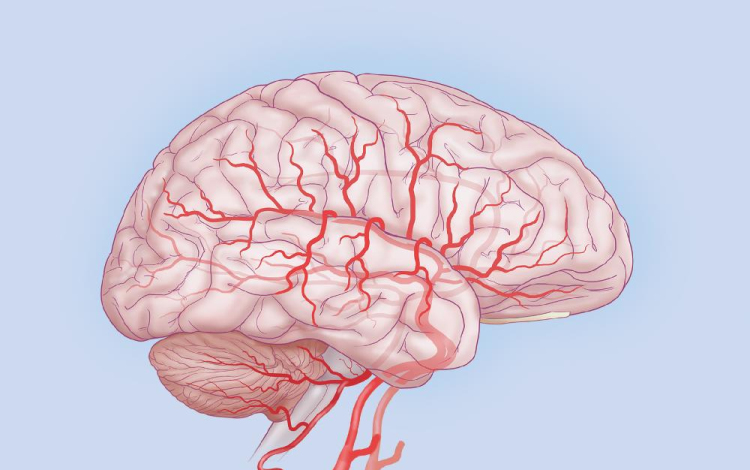

A Stanford Egyetem kutatói rohamok során jelentkező agyi aktivitást konvertáltak zenévé.

Dr. Josef Parvizi neurológus és Chris Chafe professzor, zenekutató mintegy száz elektróda segítségével regisztrálta a rohamok során keletkező agyi aktivitást, és a mintázatot zenévé alakították át. Az egyes hullámokhoz az emberi hangtartományhoz közeli hangjegyeket rendelve jutottak el az agy zenéjéig.

A módszer során a hagyományos módszert jelentő eeg-vel térképezték fel a normál aktivitás, illetve a görcsroham során jelentkező elektromos hullámokat, melyek az idegsejtek kisülése miatt jönnek létre.

A módszer jelentősége túlmutathat egy érdekes kutatáson, ugyanis az így kapott hallgatózási lelet alapján könnyűszerrel el lehet különíteni a rohamos aktivitást a normál működésre jellemzőtől. A kutatók szerint az „agyi sztetoszkóp” az epilepsziás betegek diagnosztikájában jelent pontosabb alternatívát. A fejlesztés az egyetem Bio-X Interdiszciplináris Programjának keretein belül zajlott, mely 2000 óta fut, és mintegy 141 tudóst foglalkoztat.